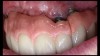

(14. and 15.) Photograph of fractured right lateral incisor taken with a smartphone and an EALS device during patient presentation for emergency treatment shown with accompanying radiograph.

Emergency visits are a common and unpredictable occurrence at nearly all dental practices (Figure 14 and Figure 15). When an emergency occurs, the patient's provider may not always be available to evaluate and initiate treatment. In a similar manner, new patients of record frequently present with oral conditions that require the attention of a dental specialist who may only be available at another clinic (Figure 16 and Figure 17). For many of these patients, immediate access to care may be limited, and if a patient is experiencing discomfort, time will be a critical factor in regard to initiating a proposed plan of action. The use of a smartphone with an EALS can allow the clinical staff to rapidly acquire intraoral photographs or a video and transmit these images and other information via encrypted text message or secure e-mail to anywhere in the world for immediate consultation. The combination of telecommunications and dentistry is known as teledentistry,13 which has been shown to impart significant benefits to patients and providers in the fields of oral medicine,14 oral and maxillofacial surgery,15 endodontics,16 prosthodontics,17 periodontics,18 pediatrics,19 orthodontics,20 and oral hygiene.21